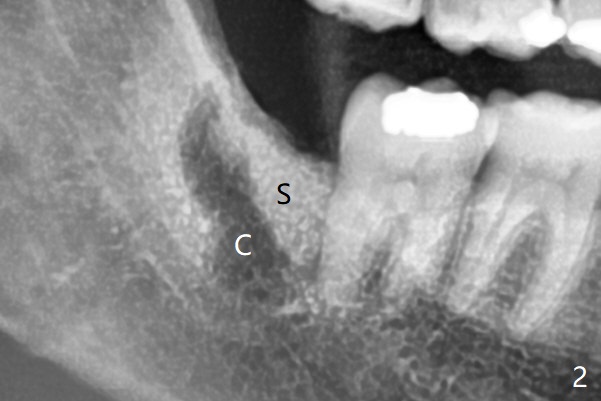

之后在牙槽窝远中,近中放置胶原塞(图二:C)和粘性骨粉(S),上面覆盖PRF,使用4-0 PGA缝线,近中伤口缝合不紧。

智齿牙龈出血       Last     Next

Xin Wei, DDS, PhD, MS 1st edition 06/07/2021, last revision 07/31/2021